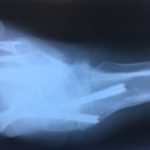

RTG przed operacją